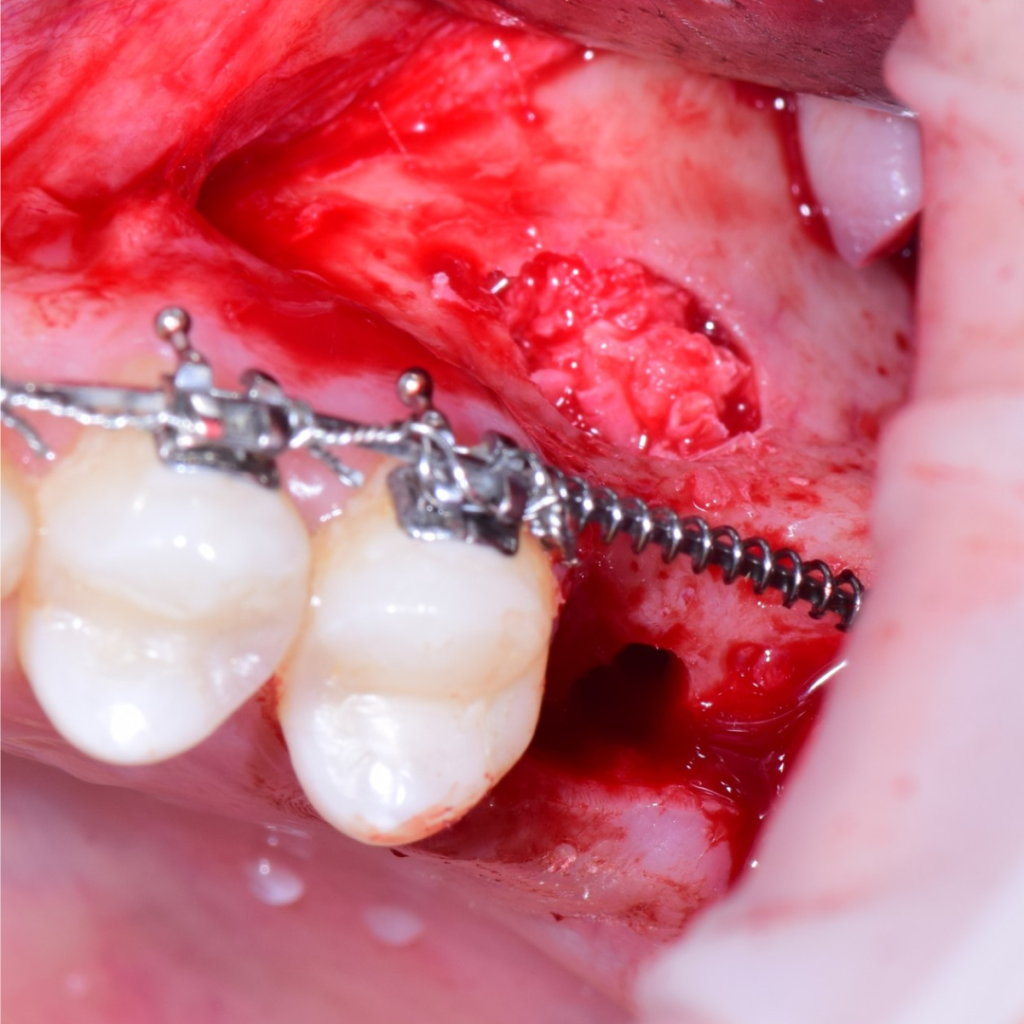

По результатам диагностики принято решение провести синус-лифтинг с помощью боров SinPro. В ходе вмешательства установлены имплантаты AnyRidge и AnyOne с первичной стабилизацией 40 Ncm.